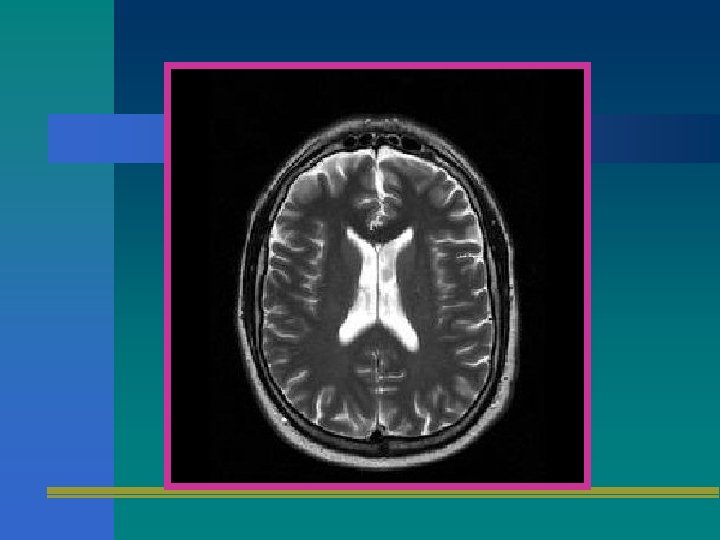

SECUENCIA T 2 • UTILIZA UN ECO SPIN CON TE LARGO Y TR LARGO. • ES MUY SUSCEPTIBLE A LOS CAMBIOS EN EL CONTENIDO DE AGUA Y POR ENDE AL EDEMA Y LA INFLAMACION.